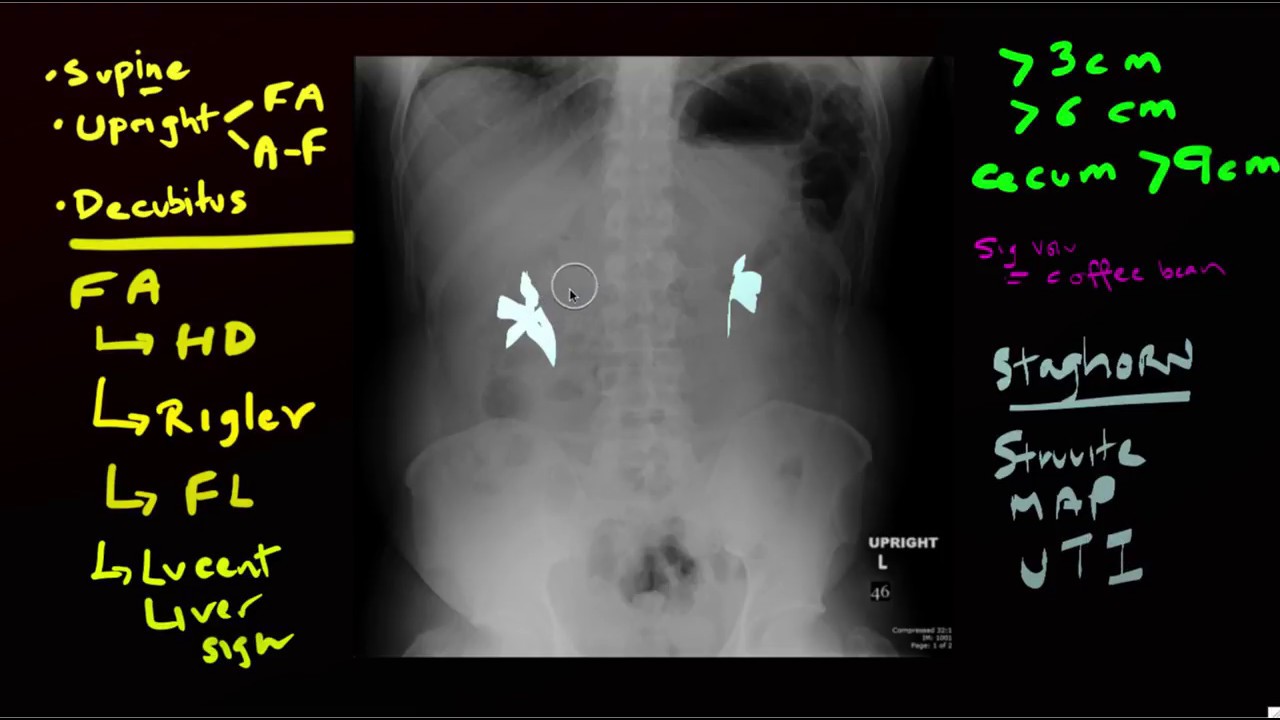

Lucent Liver Sign X Ray . Rigler's sign — air outlining both sides of the bowel wall. Rigler's sign — air outlining both sides of the bowel wall. While originally described in infants as a clue to pneumoperitoneum visible on supine abdominal radiographs [1], extraluminal gas. The lucent liver sign is represented by a reduction of hepatic radiodensity on supine radiograph when there is a collection of free. On the supine radiographs, the blacker density of the large intraperitoneal free gas anterior to the ventral. The rigler sign is identified with air present on both sides of the abdominal wall (arrowhead). The lucent liver sign is identified.

Rigler's sign — air outlining both sides of the bowel wall. The lucent liver sign is represented by a reduction of hepatic radiodensity on supine radiograph when there is a collection of free. The rigler sign is identified with air present on both sides of the abdominal wall (arrowhead). Rigler's sign — air outlining both sides of the bowel wall. The lucent liver sign is identified. While originally described in infants as a clue to pneumoperitoneum visible on supine abdominal radiographs [1], extraluminal gas. On the supine radiographs, the blacker density of the large intraperitoneal free gas anterior to the ventral.

Lucent Liver Sign X Ray On the supine radiographs, the blacker density of the large intraperitoneal free gas anterior to the ventral. The lucent liver sign is represented by a reduction of hepatic radiodensity on supine radiograph when there is a collection of free. The rigler sign is identified with air present on both sides of the abdominal wall (arrowhead). Rigler's sign — air outlining both sides of the bowel wall. On the supine radiographs, the blacker density of the large intraperitoneal free gas anterior to the ventral. Rigler's sign — air outlining both sides of the bowel wall. While originally described in infants as a clue to pneumoperitoneum visible on supine abdominal radiographs [1], extraluminal gas. The lucent liver sign is identified.

EPOS™ Lucent Liver Sign X Ray The rigler sign is identified with air present on both sides of the abdominal wall (arrowhead). On the supine radiographs, the blacker density of the large intraperitoneal free gas anterior to the ventral. Rigler's sign — air outlining both sides of the bowel wall. The lucent liver sign is represented by a reduction of hepatic radiodensity on supine radiograph when. Lucent Liver Sign X Ray.

Abdomen Case 7 Lucent Liver Sign X Ray Rigler's sign — air outlining both sides of the bowel wall. The lucent liver sign is represented by a reduction of hepatic radiodensity on supine radiograph when there is a collection of free. Rigler's sign — air outlining both sides of the bowel wall. On the supine radiographs, the blacker density of the large intraperitoneal free gas anterior to the. Lucent Liver Sign X Ray.